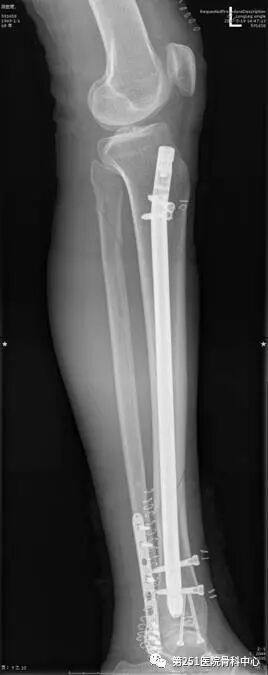

病例1:男性,40岁,车祸伤,胫腓骨多段骨折。

![]()